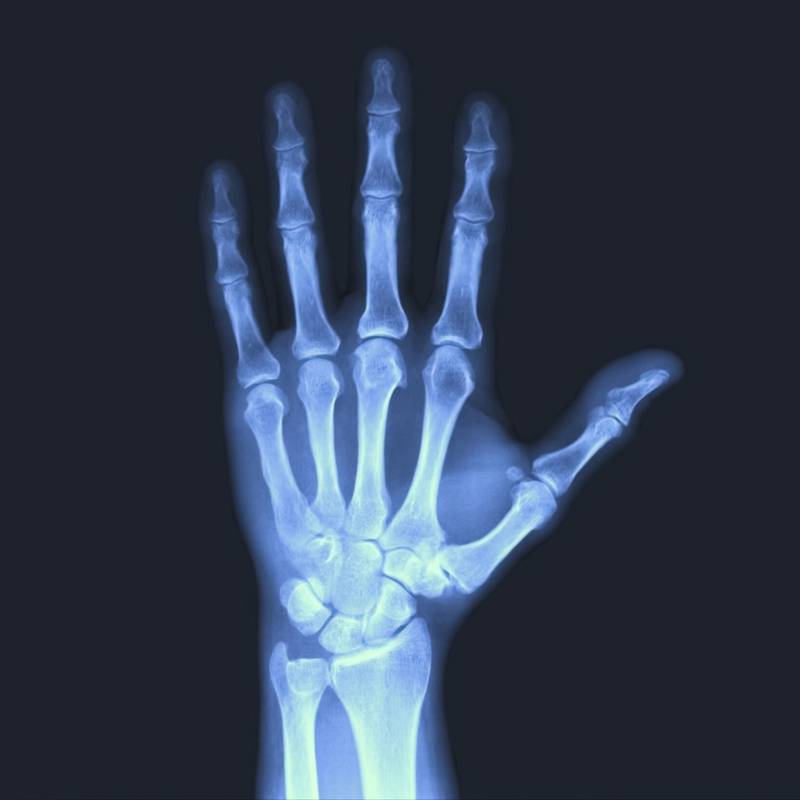

Digunakan untuk menilai struktur tulang tangan.